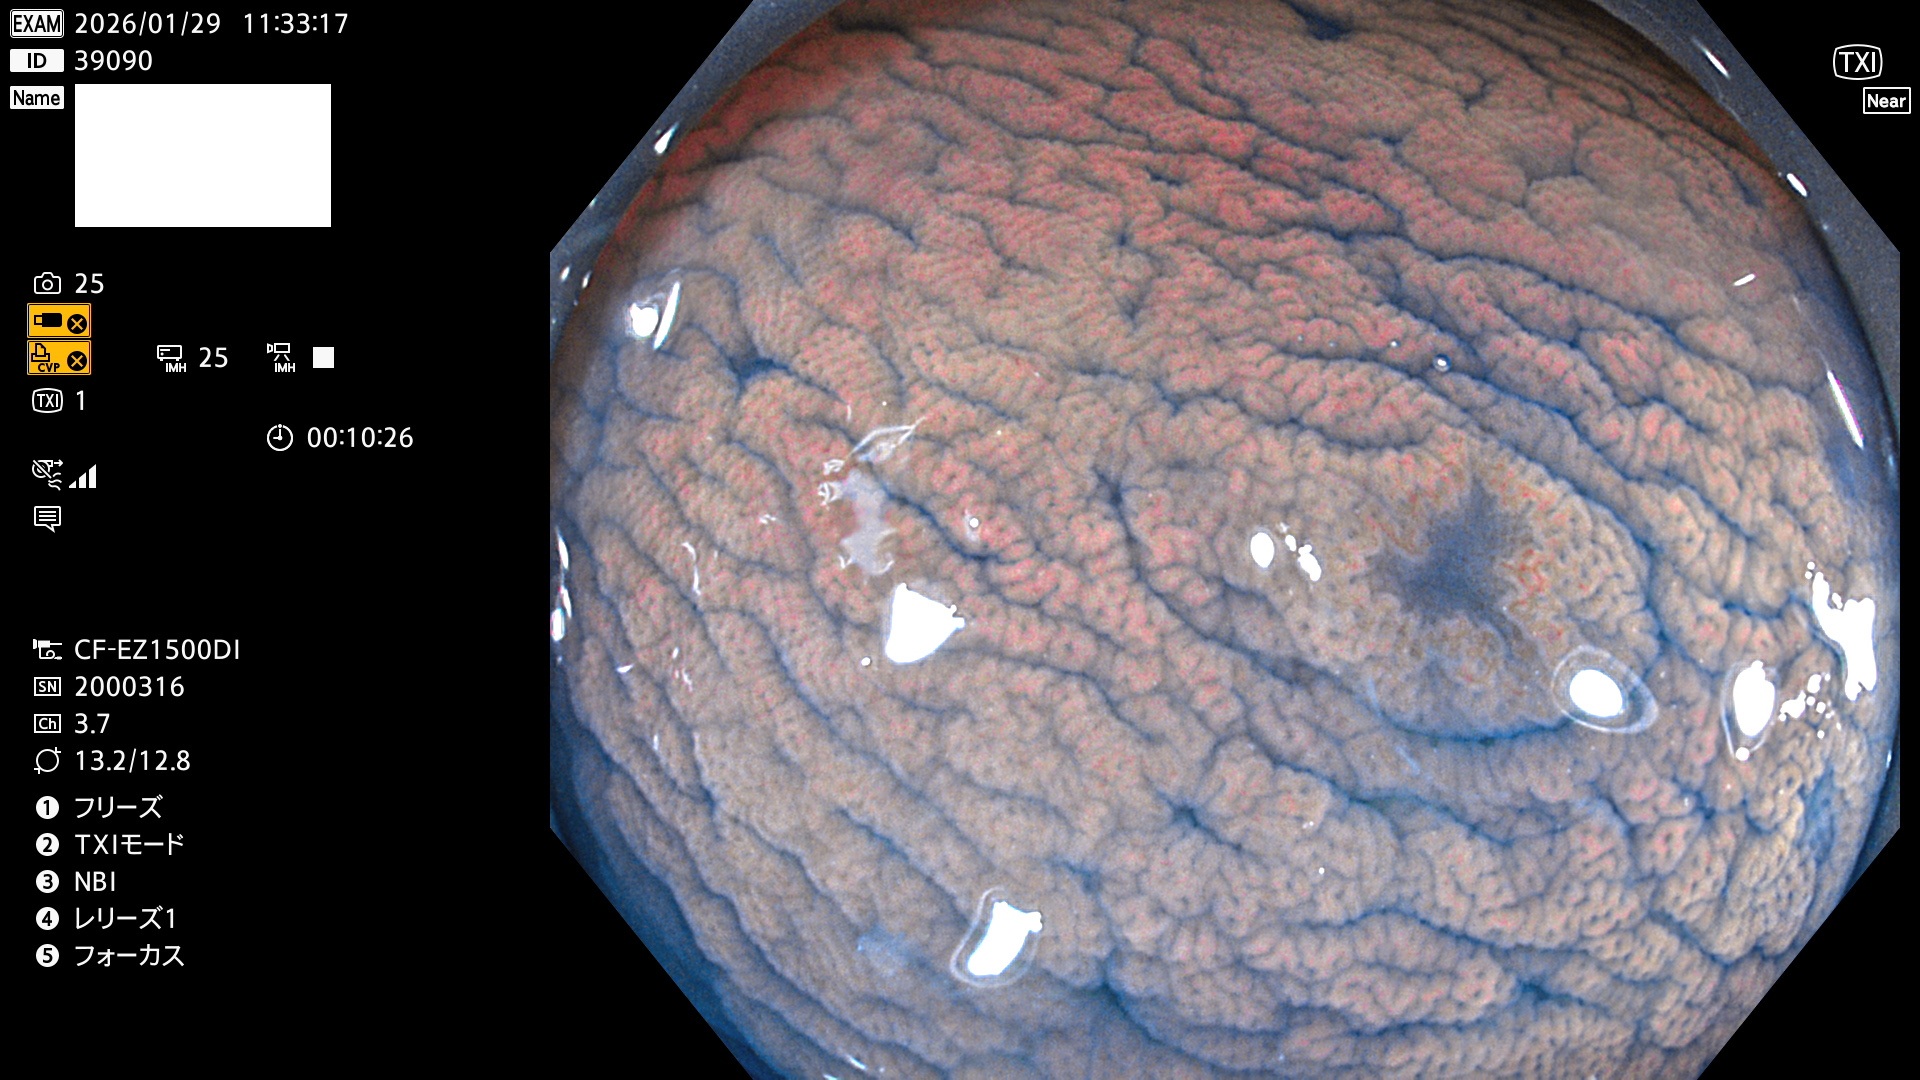

完全に平坦な物をUb、陥凹している物をUcと呼びます。Ubは認識が困難で、Ucはびらん(炎症)と紛らわしいために見落とされやすく、「内視鏡後・大腸癌」の原因になります。

毎週の検査(木・金・土・日)に発見されたUbとUc型・腺腫を、その週の日曜の夜にUPし1週間、提示します。

2026年1月29日〜2月1日の4日間(40件)10個 (Uc_ADR=10個/40人=25%)